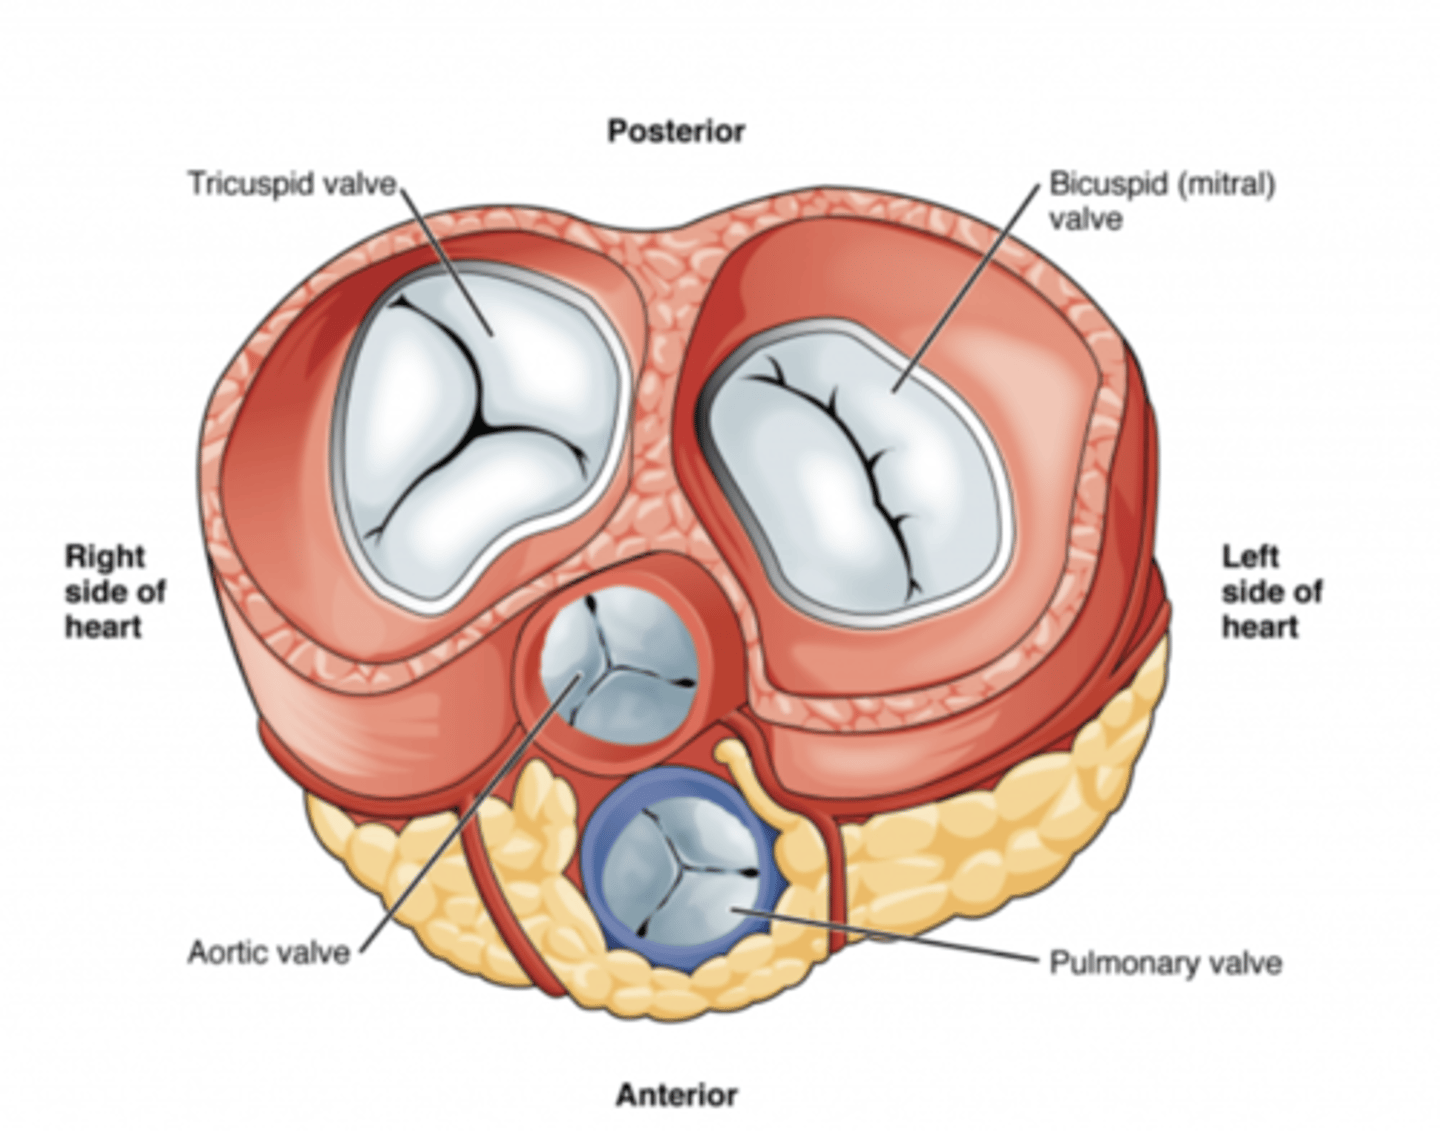

What are the valves separating atrium and ventricle?

. Tricuspid valve (right atrioventricular valve, 3 cusps)

. Mitral or bicuspid valve (left atrioventricular valve, 2 cusps)

AXIAL VIEW OF THE HEART

What are the 3 cusps of the tricuspid valve?

Anterior

Posterior

Septal

What are the four valves in the heart?

Tricuspid

Mitral or bicuspid

Pulmonary

Aortic

What valves are assuring the AV unidirectional flow?

Tricuspid (right)

Mitral or bicuspid (left)